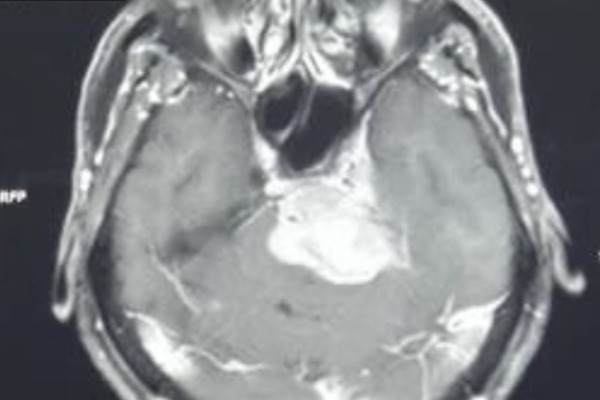

斜台部・錐体骨部腫瘍 症例 頭蓋底部 髄膜腫

鞍上部腫瘍 頭蓋底部

鞍上部腫瘍とは、トルコ鞍と呼ばれる両目の奥、正中部(真ん中)に存在する脳下垂体と呼ばれる小さな器官が入っている場所の上にできる腫瘍の総称です。このページでは鞍上部腫瘍についての治療から合併症についてまで詳しく説明していきます。